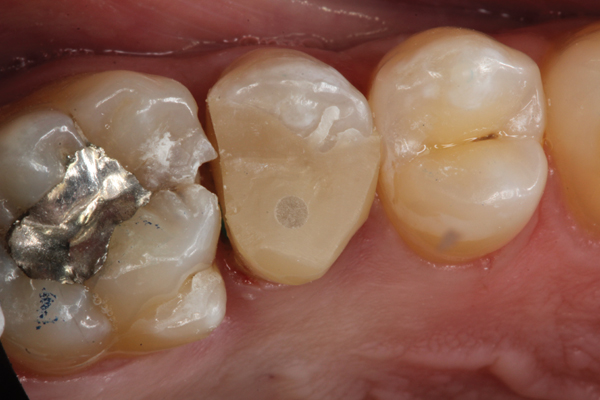

Higher viscosity bulk-fill composites can be used up to the occlusal surface, however. Two clinical cases using the bulk-fill composites Tetric EvoCeram Bulk Fill and SonicFill are presented in Figure 2 through Figure 6. Limitations when placing a high-viscosity bulk-fill composite include difficulty of condensing and esthetic restraints. Condensing a high-viscosity resin composite ensures adequate adaptation to the tooth preparation and sufficient interproximal contacts. Condensing 4 mm of composite is more difficult than condensing 2 mm. To ensure adequate interproximal contacts, a sectional or circumferential matrix with an inciso-gingival curvature can be used to obtain a tight area of contact gingival to the marginal ridge. A ring should be used to help separate the teeth and improve the tightness of the contact area.

(2.) Preparation of tooth No. 31.

Figure 2

(3.) Restoration of tooth No. 31.

Figure 3